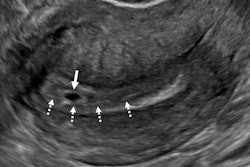

Fetal nuchal translucency is an ultrasound exam performed in the first trimester of pregnancy. It helps determine the risk of congenital conditions like Down syndrome being developed in fetuses. Specifically, it screens for trisomies 21 and 18 and other conditions.

A cutoff of 3.5 mm or greater is used as a marker for common and uncommon aneuploidies (i.e., missing chromosomes) as well as for a wide variety of genetic syndromes and structural anomalies. With this cutoff point, follow-up exams such as prenatal cell-free DNA screening or cytogenetic testing are recommended.